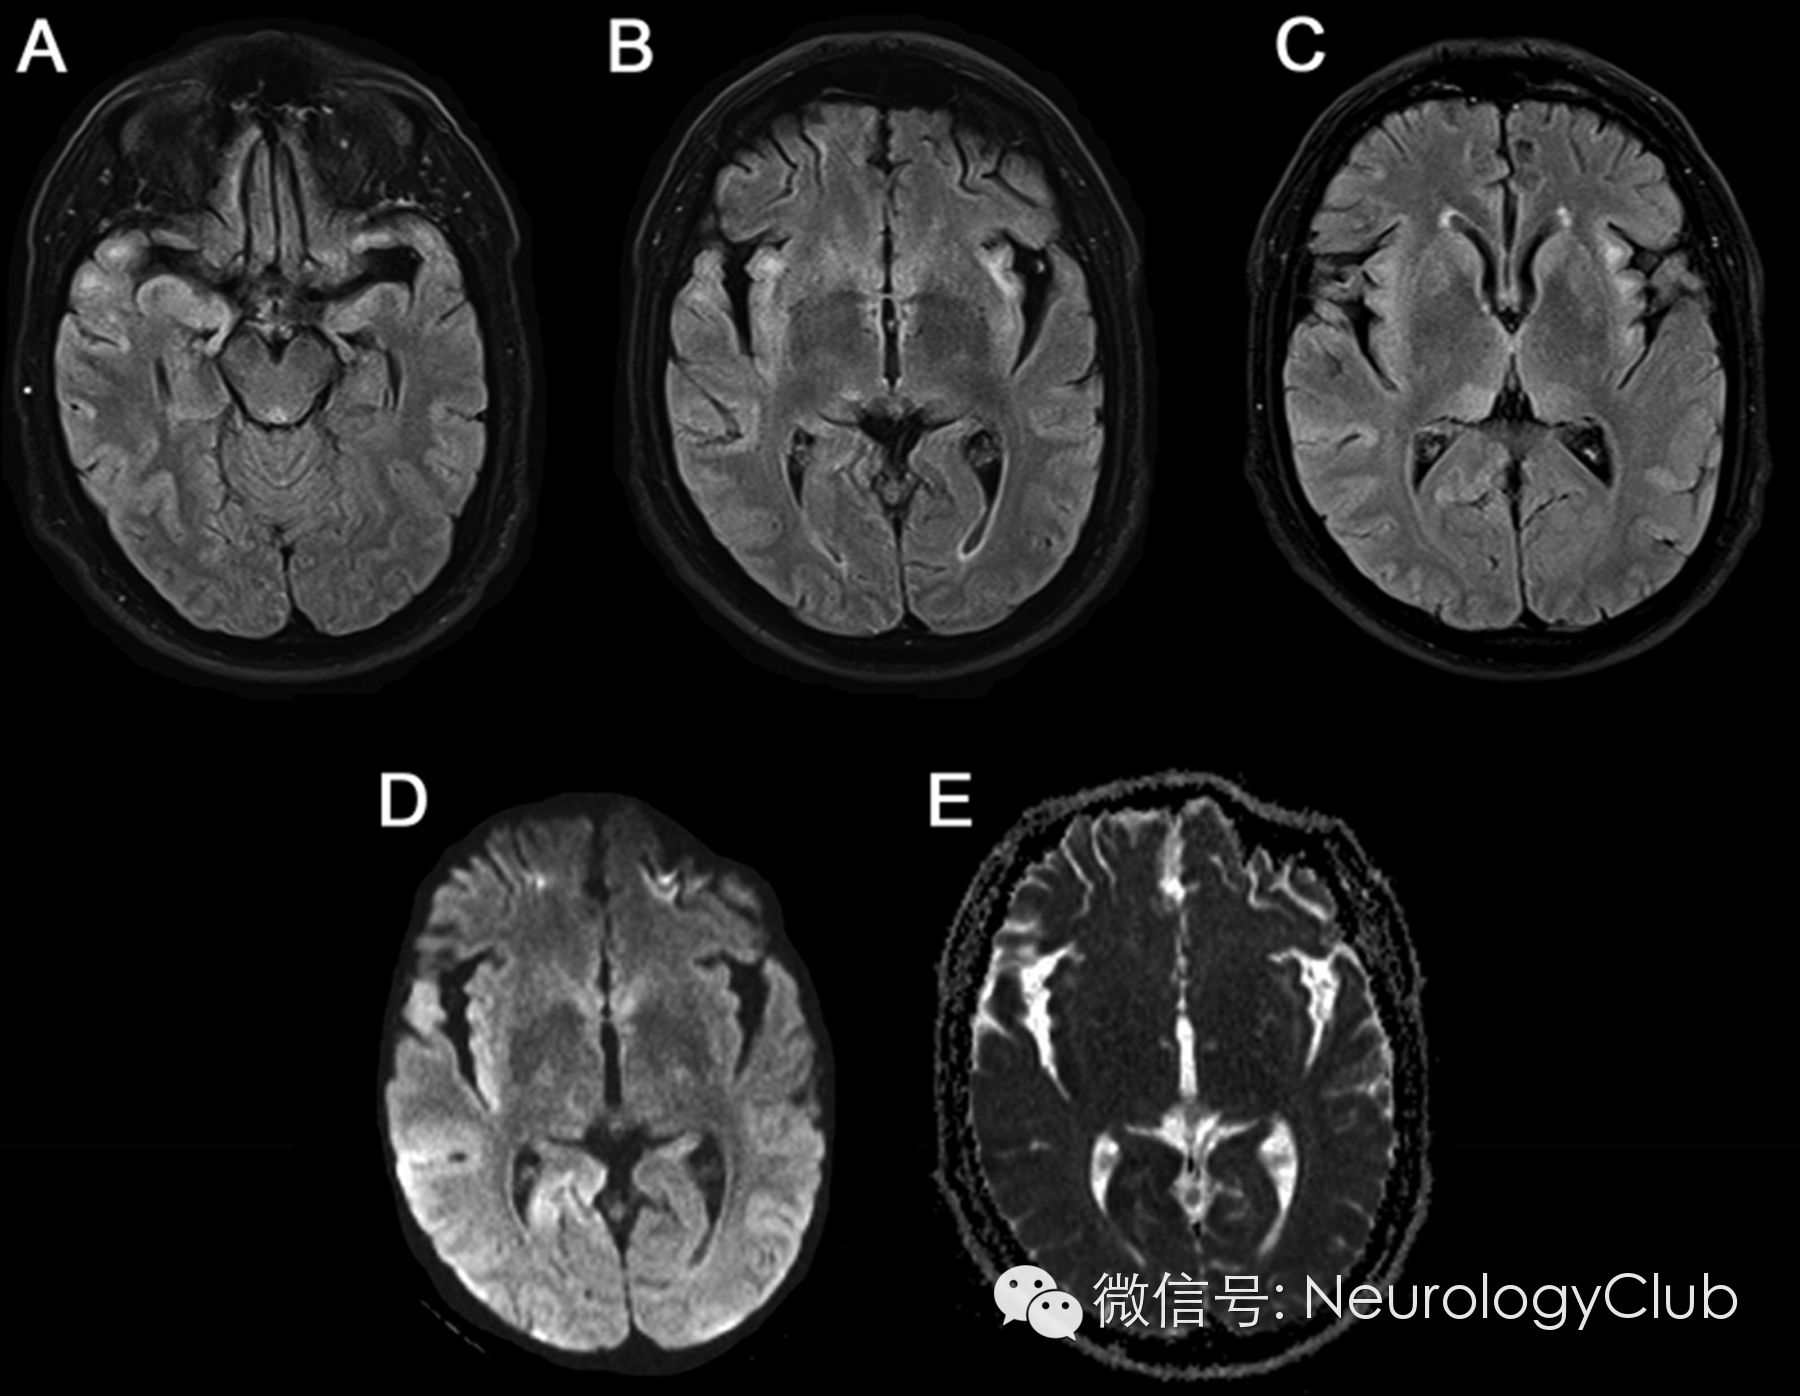

头颅MRI示皮质区和丘脑多发病变,部分弥散受限。

(A-C:黑水像示双侧颞叶内侧面,岛叶,丘脑枕部以及右侧颞枕叶皮质病灶高信号;D-E:DWI及ADC示右侧颞枕叶皮质和右侧岛叶病灶弥散受限)